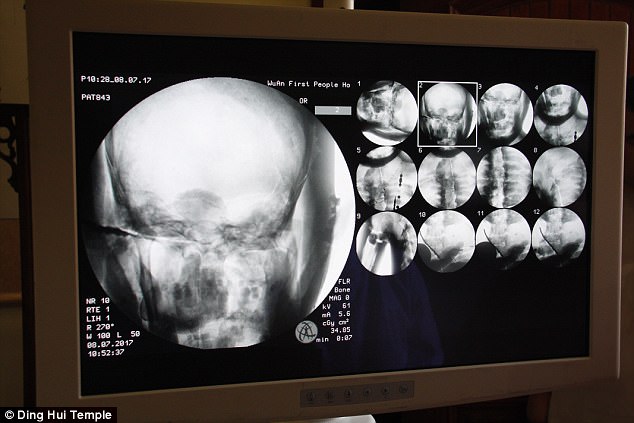

Sự kiện gây chấn động diễn ra vào ngày 8 tháng 7 năm 2017, khi các nhà khoa học tiến hành chụp CT để kiểm tra bên trong "bức tượng" này trước sự chứng kiến của giới truyền thông và đông đảo người dân. Kết quả hình ảnh quét được đã khiến tất cả những người có mặt phải bàng hoàng. Các bác sĩ xác nhận rằng bên dưới lớp mạ vàng, nhà sư Ci Xian vẫn giữ được bộ xương nguyên vẹn cùng một bộ não hoàn chỉnh.

Kết quả hình ảnh từ máy quét đã khiến toàn bộ giới khoa học và những người chứng kiến phải kinh ngạc đến mức sững sờ. Các bác sĩ xác nhận rằng nhà sư Ci Xian vẫn còn giữ được một bộ xương hoàn chỉnh cùng một bộ não nguyên vẹn.

Bác sĩ Wu Yongqing, người trực tiếp tham gia buổi kiểm tra cho biết xương của ngài khỏe mạnh và rõ ràng như một người bình thường. Từ xương hàm trên, răng, xương sườn, xương sống cho đến tất cả các khớp đều vẫn còn nguyên vẹn một cách khó tin. Sự tồn tại hoàn hảo của thi hài sau hơn 1.000 năm đã chứng minh kỹ thuật ướp xác đỉnh cao thời bấy giờ, tạo nên một hiện tượng chấn động khiến cả thế giới phải chú ý.